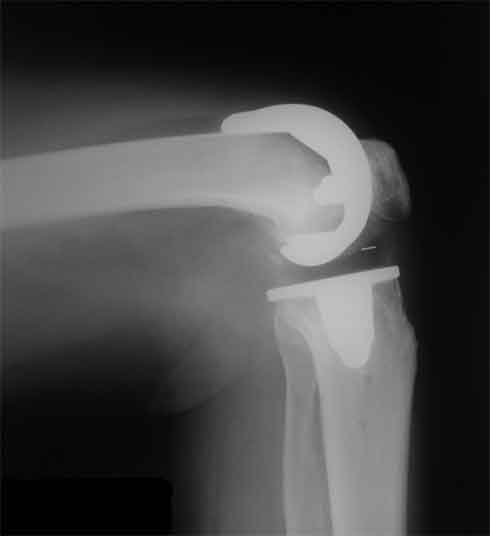

Стрессовый снимок

Оперирована пациентка 42 лет, избыточного веса. Выполнено б/ц протезированние коленного сустава эндопротезом LCS. Послеоперационный период гладкий, в срок 2 мес. после операции объем движений удовлетворительный, сгибание до острого угла, разгибание полное. В 3,5 мес. во время падения подвернула ногу, после чего появилась. клиника медиолатеральной нестабильности. В течении 3 недель фиксация в туторе. При повторном осмотре жалобы на дискомфорт в коленном суставе, «щелканье», неустойчивость в суставе. Вопросы/варианты дальнейшей тактики лечения пациентки.

1) Существует ли способы восстановления внутренней боковой связки на фоне протезированного коленного сустава и как добиться равномерного ее натяжения при всех углах сгибания.

2) Ревизия с установкой более связанного протеза (constrained)